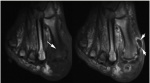

Рис. 4. Нейропатия стопы на МРТ

Нарушение нейрорегуляции (аутосимпатэктомия) приводит к отеку мышц и подкожно-жировой клетчатки.

Т2 – подкожный и мышечный отек;

- отсутствие усиления после контрастирования гадолинием.